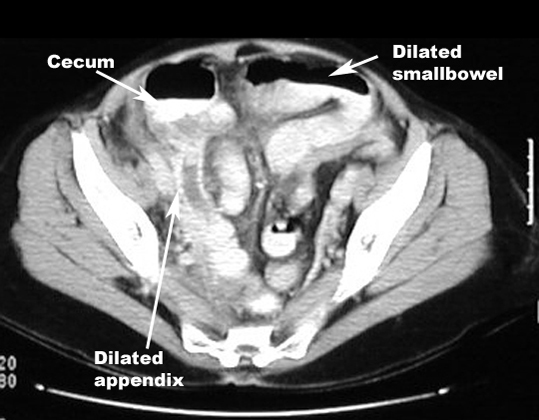

CT: Highly accurate

Signs: